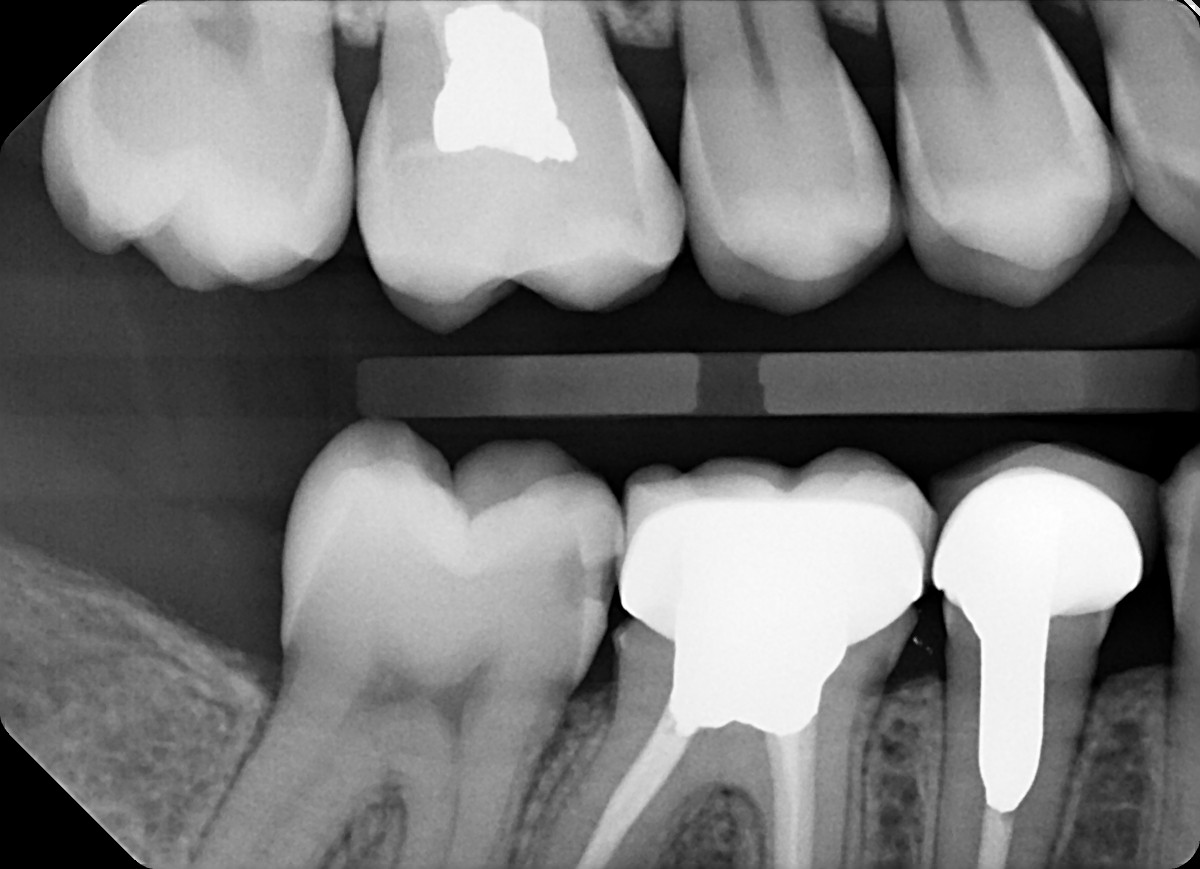

8 / 35

8. On which surface a recurrent caries can be detected?

under crowns the recurrent caries can easily become cavtated ad they are seen more radiolucent

9 / 35

9. On which surface a recurrent caries can be detected?

although distal tooth # 4.6 is risky but as the rest are recurrent this option is safe to select